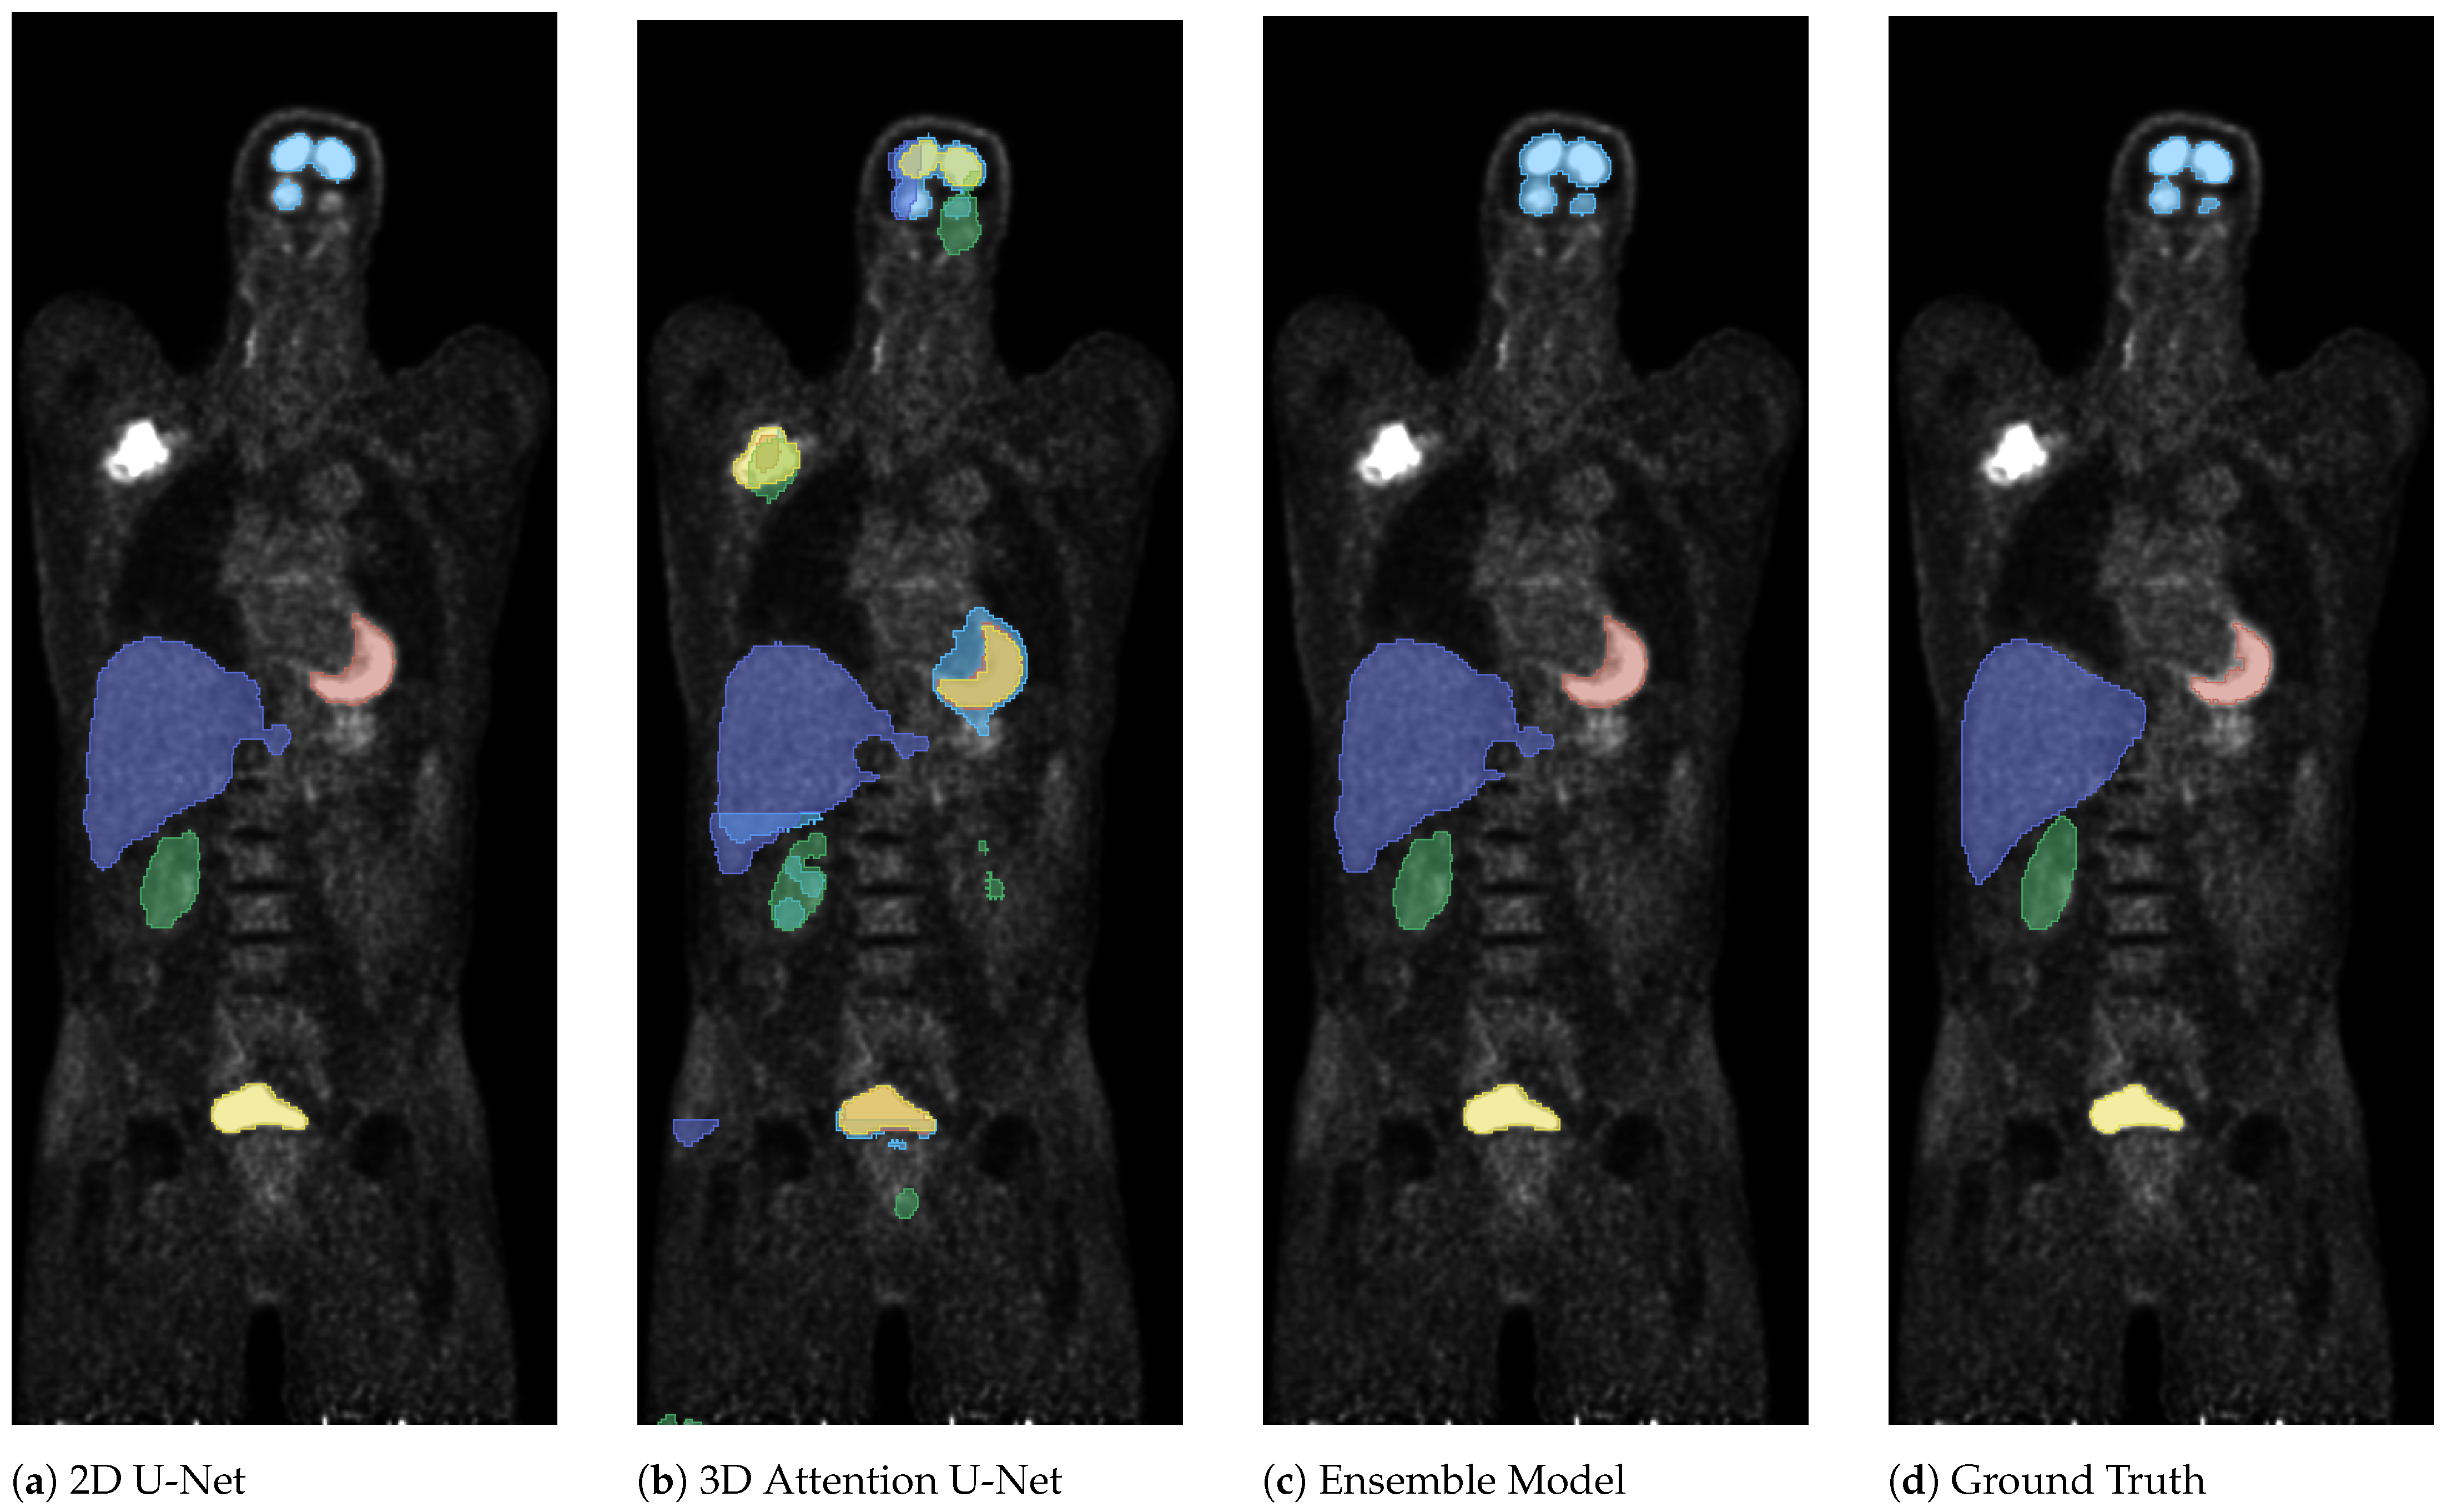

3. Results